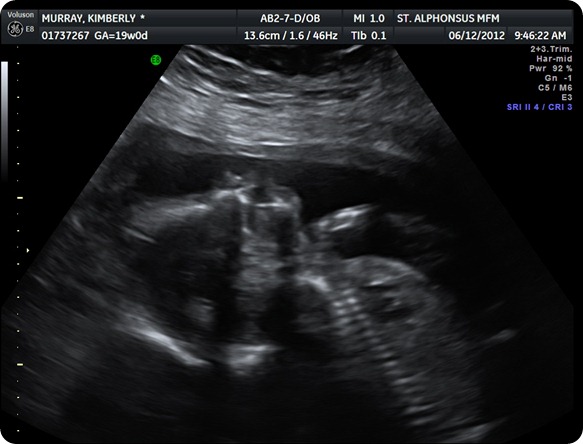

It’s a GIRL!!!! June 12th

We are excited to announce that we are having another baby GIRL!!! We are so excited, but I have to admit I really, really wanted a boy. Rigg wanted and knew it would be a girl. Peyton still thinks it is a boy. When the tech told us it was a girl, she pouted and was not happy. When we tell her she is having a sister she says “ I no having a sister, I having a boy." She did so well at the appointment, but can’t say the same about this little baby girl. She would not give us a good profile picture and was moving and flipping all over the place. Other than that she is looking great! We feel very happy and blessed!